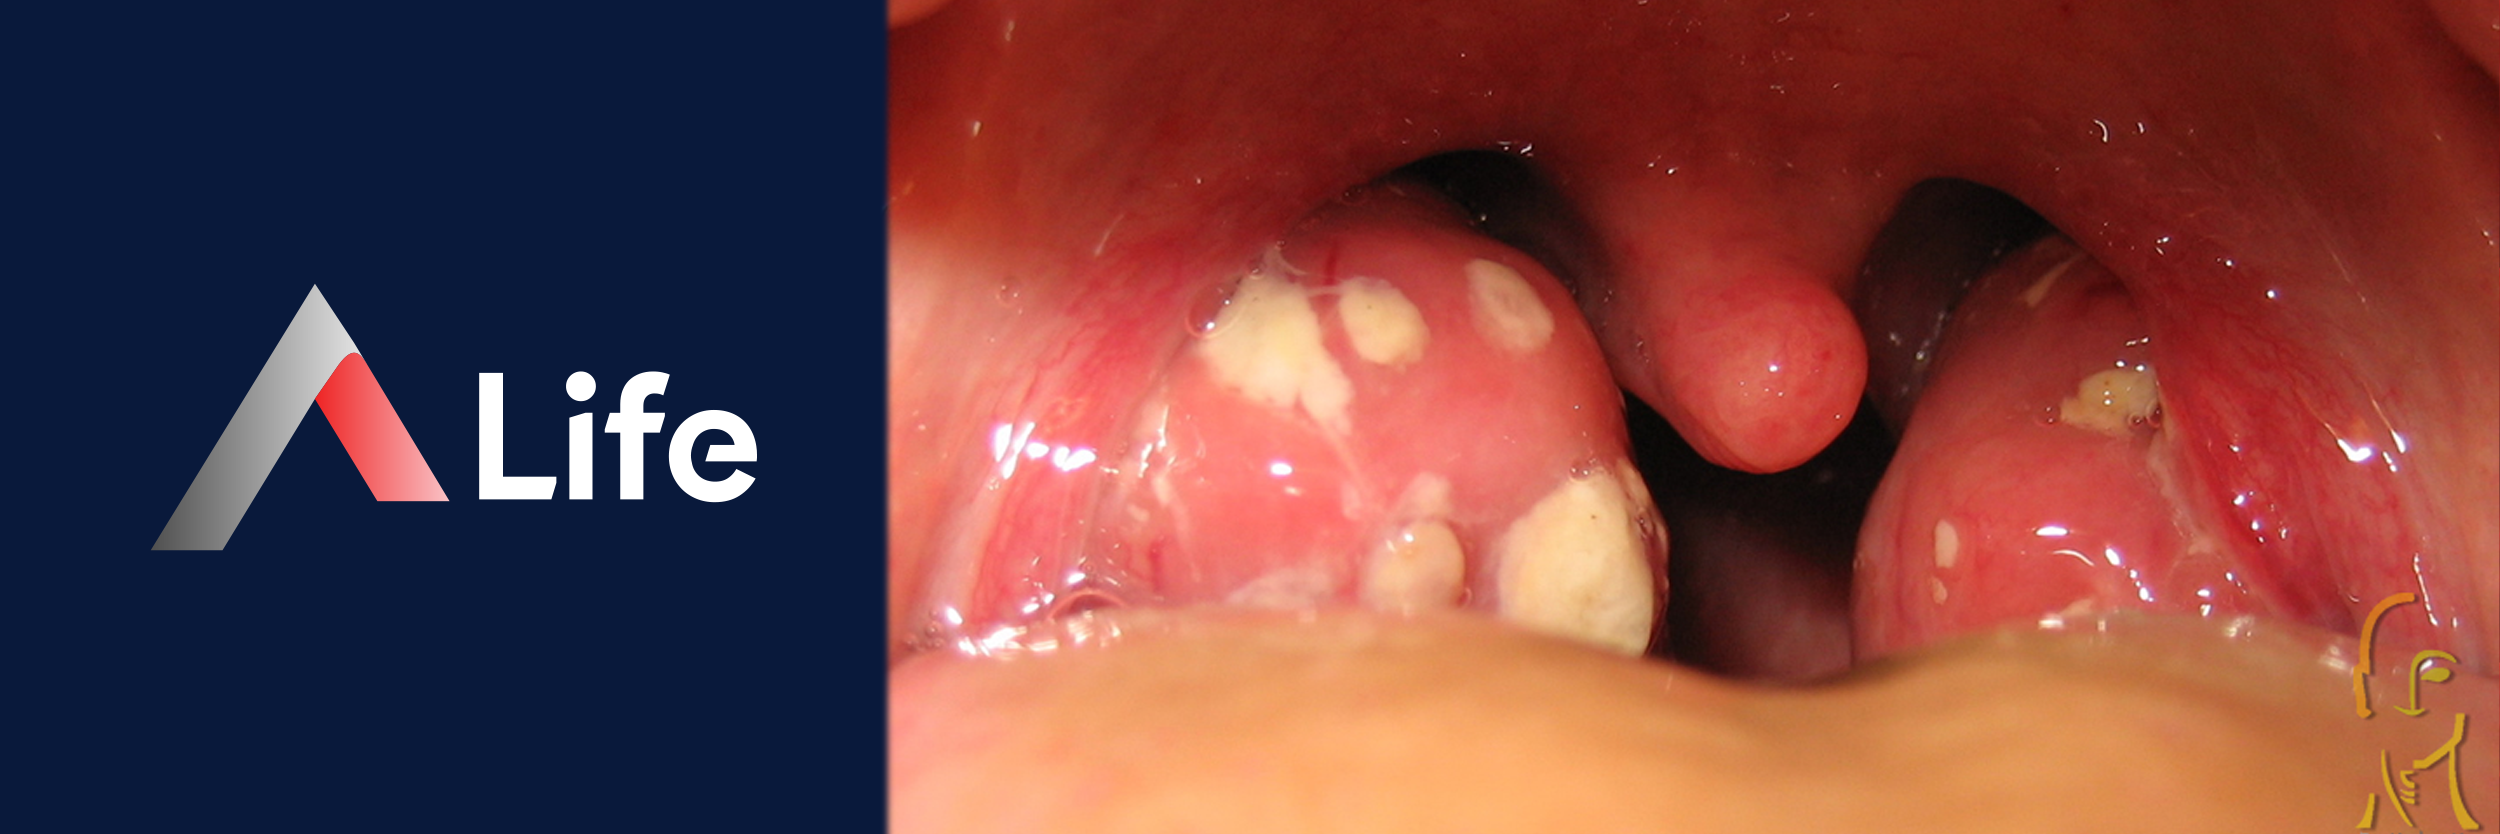

Tıbbi adıyla tonsillit, boğazın arkasındaki bademciklerin enfekte olmasıdır. Bu enfeksiyon, virüsler ve bakteriler nedeniyle oluşur. Bademcik iltihabı yaygın bir hastalıktır. Çocuklarda ve yetişkinlerde görülebilen bu rahatsızlık, özellikle soğuk havalarda daha sık karşılaşılan bir sağlık sorunudur.

Yüksek ateş, yutma zorluğu, boğazda beyaz yaralar ve baş ağrısı gibi belirtilerle görülen bir enfeksiyon vardır. Bu enfeksiyon, erken teşhis ve tedavi gerektirir. Ciddi komplikasyonlar yaşamamak için bu önemlidir.

Boğazda beyaz yara oluşumu genellikle bakteriyel enfeksiyonlara işaret eder. Bu durumda boğaz kültürü alınarak tanı netleştirilmelidir.

Bazı hastalarda bademciklerin üzerinde beyaz iltihap oluşur. Bu oluşumlar bakteriyel kaynaklı ise hekimin önerdiği şekilde bademcik iltihabı temizlenmesi yapılabilir. Ancak evde kendi kendine bademcik iltihabı patlatma kesinlikle önerilmez, çünkü bu enfeksiyonun yayılmasına ve komplikasyonlara yol açar.